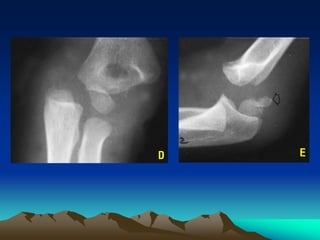

Phaân loaïi theo DeLee vaø cs (1980): chia 3 nhoùm, döïa treân

möùc ñoä coát hoùa cuûa nhaân loài caàu (NLC) xöông caùnh tay.

- Nhoùm A: < 12 thaùng tuoåi, tröôùc khi NLC xuaát hieän, thaáy ñöôïc treân

phim X quang, chæ BSTH Harris-Salter I. Thöôøng deã boû soùt chaån ñoaùn

vì NLC chöa coát hoùa (hình A-B)

- Nhoùm B: 12 thaùng tuoåi - 3 tuoåi, NLC ñaõ xuaát hieän, vaãn chæ BSTH

Harris-Salter I (hình C)

- Nhoùm C: 3 - 7 tuoåi, thöôøng keøm maûnh gaõy haønh xöông ôû phía

ngoaøi, coù theå ôû phía trong vaø phía sau (hình D-E)

A

B

C

D E

X quang:

- ÔÛ treû döôùi 12 thaùng tuoåi, nhaân taïo xöông chöa xuaát

hieän. Chaån ñoaùn döïa vaøo ñaàu treân 2 xöông caúng tay vaãn

keà caän nhau, nhöng di leäch sau trong so vôùi ñaàu döôùi

xöông caùnh tay.

- ÔÛ treû treân 12 thaùng tuoåi, NLC xuaát hieän,

BSTH ñöôïc chaån ñoaùn döïa vaøo 4 ñieåm sau:

 Ñaàu treân 2 xöông caúng tay vaãn keà caän

 Ñöôøng quay - loài caàu coøn

 Toaøn boä ñaàu treân 2 xöông caúng tay vaø

NLC ñoàng boä di leäch ra sau, vaøo trong so

vôùi ñaàu döôùi xöông caùnh tay

 Ñaàu döôùi xöông caùnh tay coù daïng troøn,

ñeàu ñaën khoâng gai nhoïn (neáu coù cöïa saét

beùn, höôùng chaån ñoaùn laø gaõy treân 2 loài